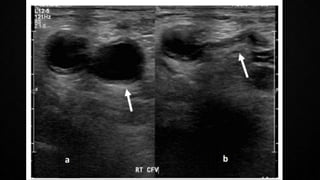

COMPRESSION ULTRASONOGRAPHY (CUS)

• PE originates from a lower limb DVT in majority of the cases

• Lower limb CUS has replaced traditional venography for diagnosis of DVT

• Sensitivity of >90% AND Specificity ~95%

• CUS shows a DVT in 30-50% of those with PE and finding a proximal DVT in a

suspected PE in sufficient to warrant anti-coagulation treatment without further testing

• In the setting of a suspected PE, CUS can be limited to a simple 4-point examination

(bilateral groins and bilateral popliteal fossae)

• Only validated diagnostic criterion is incomplete compressibility of the vein which

indicates the presence of a clot

• Flow measurements are unreliable

• Specificity improves when combined with a cardiac ultrasound